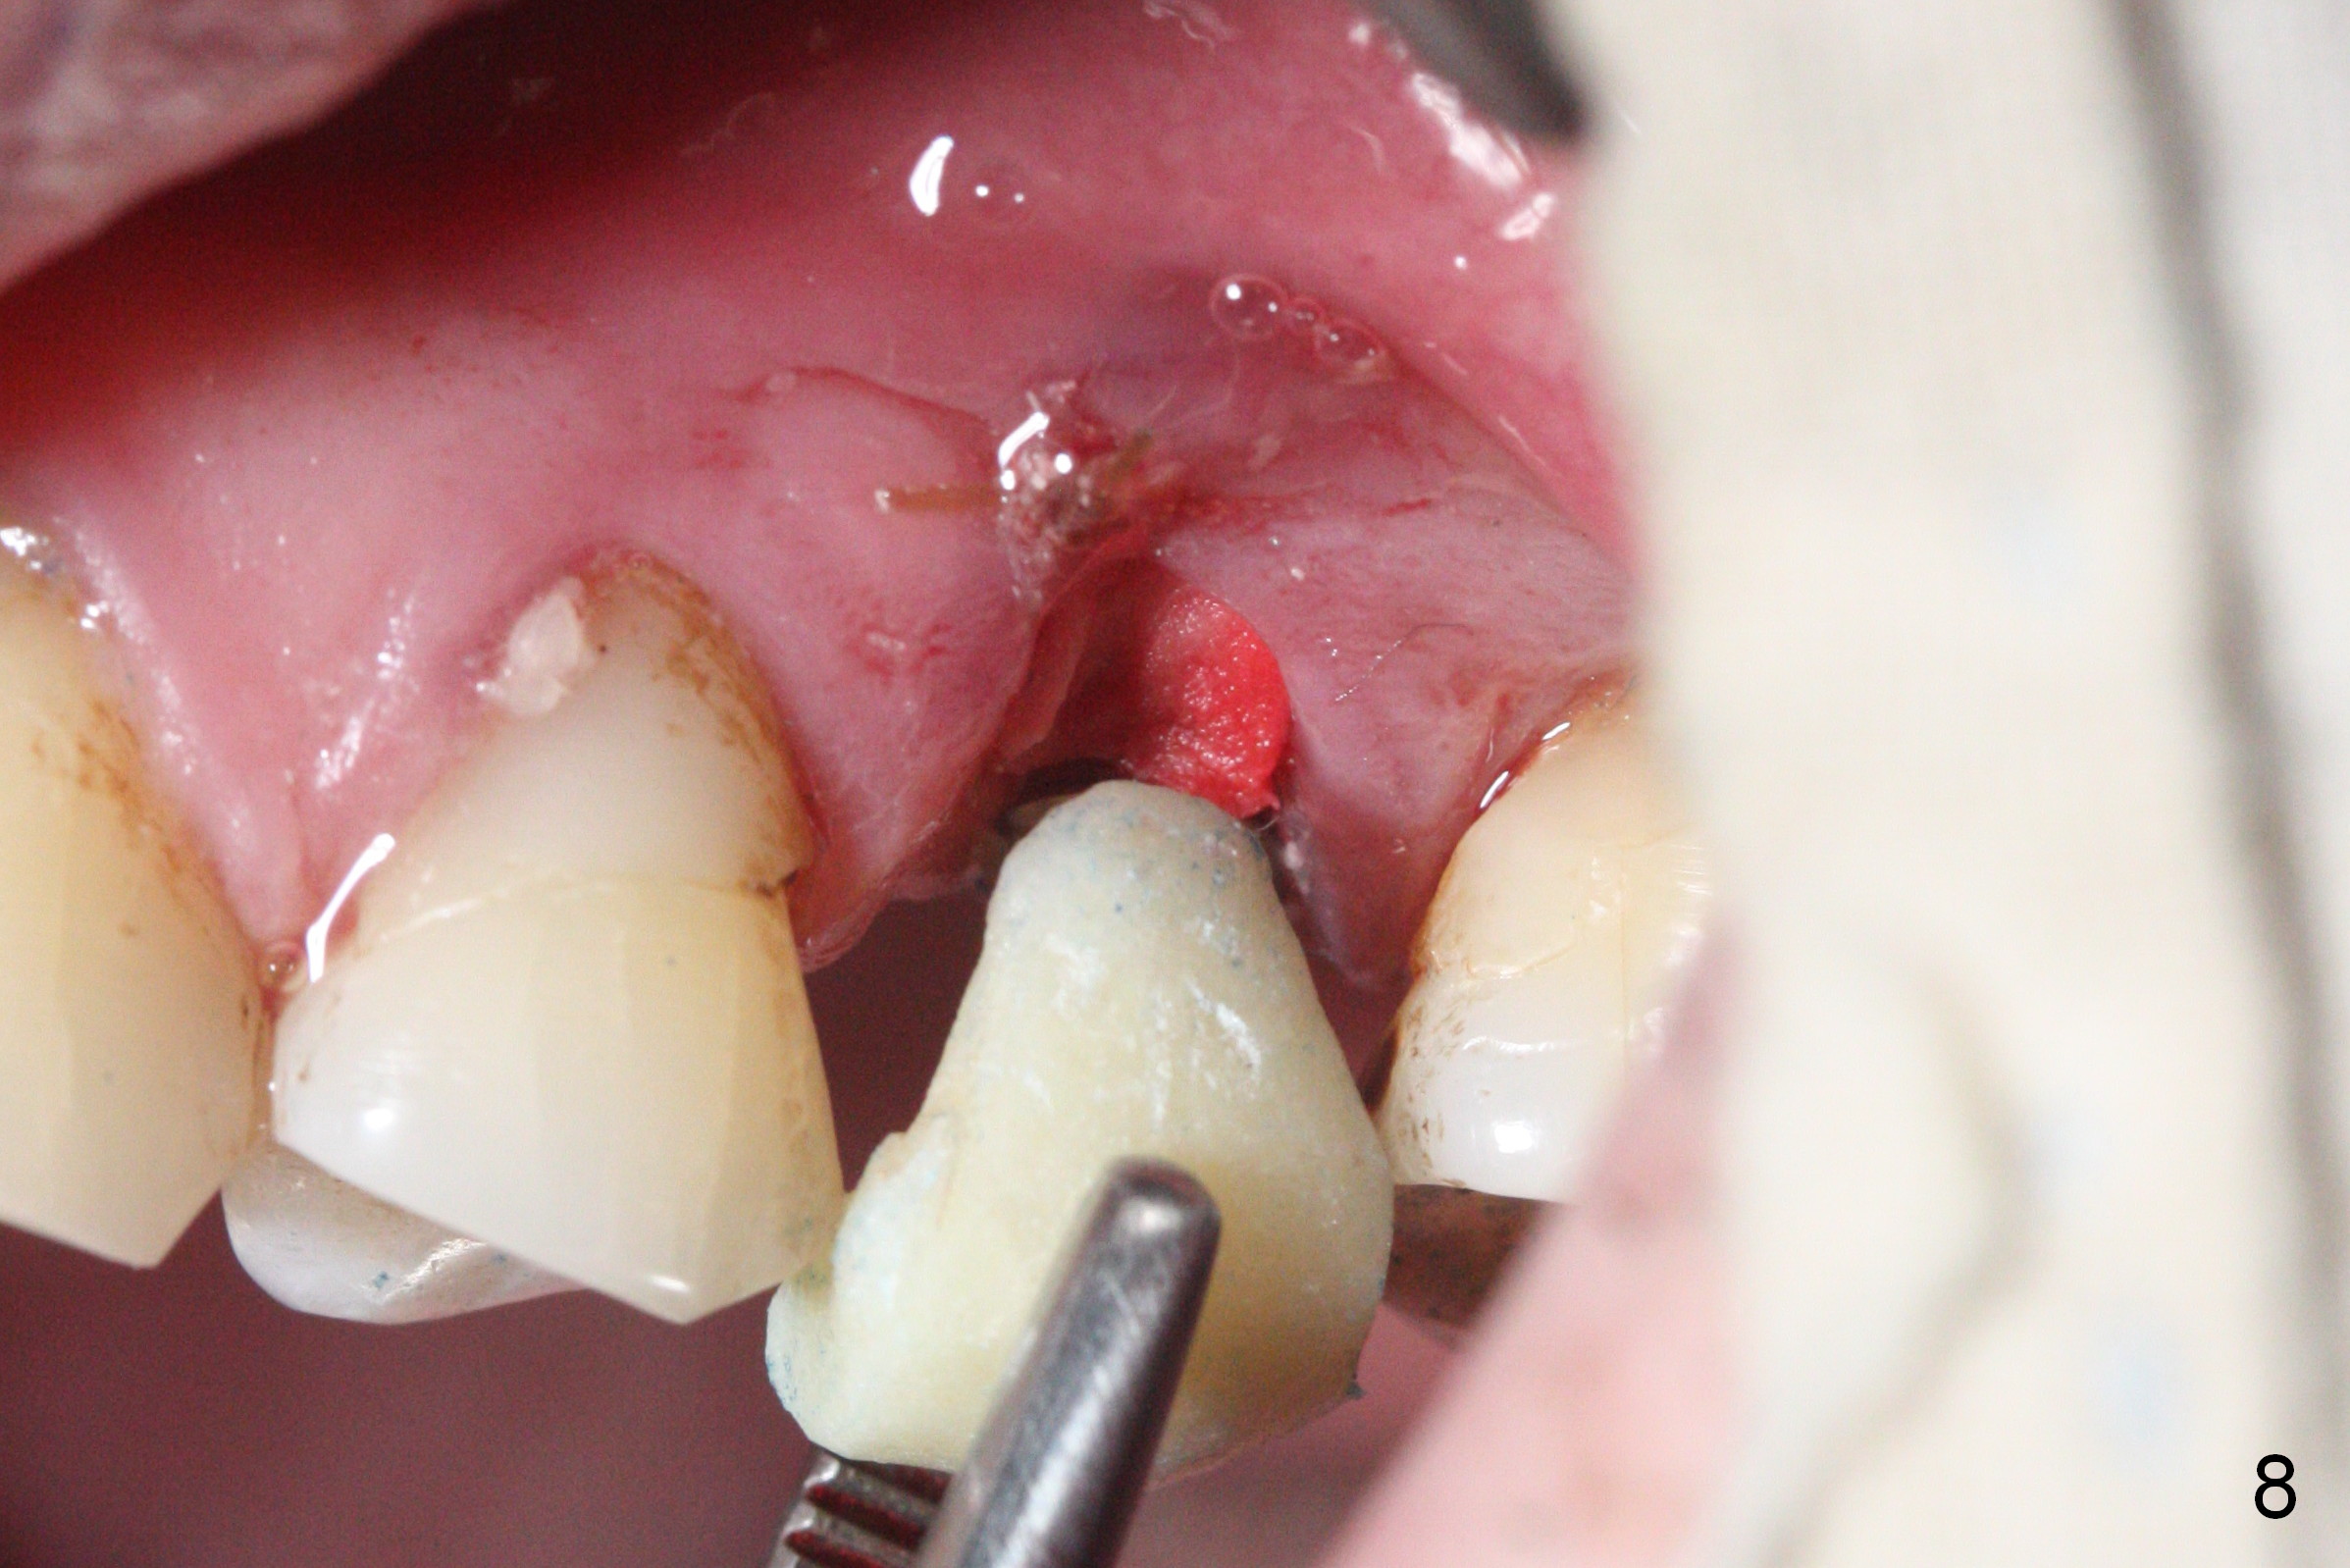

Initial osteotomy depth is 18 mm (Fig.1 green line) with 9 mm in the native bone (red line).  The bone density feels to be low.  There is at least 2 more mm bone apically (pink line).  The depth is increased by 2 mm so that when a 3.8x15 mm implant is placed, there is 10-11 mm implant/bone contact (Fig.2 red line).  There is large bony defect (Fig.3 *), which is bone grafted (Fig.4 *).  Finally a longer abutment is placed (4.5x5.5(5) in Fig.4 vs. 4.5x4(5) in Fig.2,3).  The 5 mm cuff does not look too long buccally (Fig.5) or palatally (Fig.6).   To prevent postop buccal gingival overgrowth (2), the buccal margin of an immediate provisional is subgingival (Fig.7-9 *).  Bone density between #13 and 14 appears to increase 3 months postop (Fig.10).  The implant seems to be equi-crestal (Fig.11 ^).  There seems to be more bone growth (i.e., decreasing gap) 6 months postop (Fig.12).  Impression is taken.  A crown is delivered nearly 7 months postop (08/07/2017).   While there is minimal bone loss at #13 and 15 three years and 4 months post cementation, the tooth #14 and 18 are mobile (Fig.13,14).